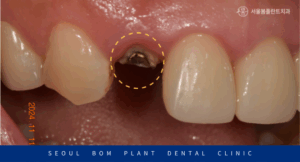

Post core를 진행한 뒤 치아를 일부 다듬은 후

인상채득을 시행하였으며,

Shade guide를 이용하여 색조를 선정하였습니다.

자연치아와 강도가 유사하고

심미적인 지르코니아 크라운으로

최종 보철물을 수복한 모습의

구강 내 사진과 파노라마 사진인데요.

자연스러운 색조와 형태로 크라운이 제작되어

수복한 치아가 어디인지 모를 정도로

심미적으로 개선된 것을 확인할 수 있었습니다.